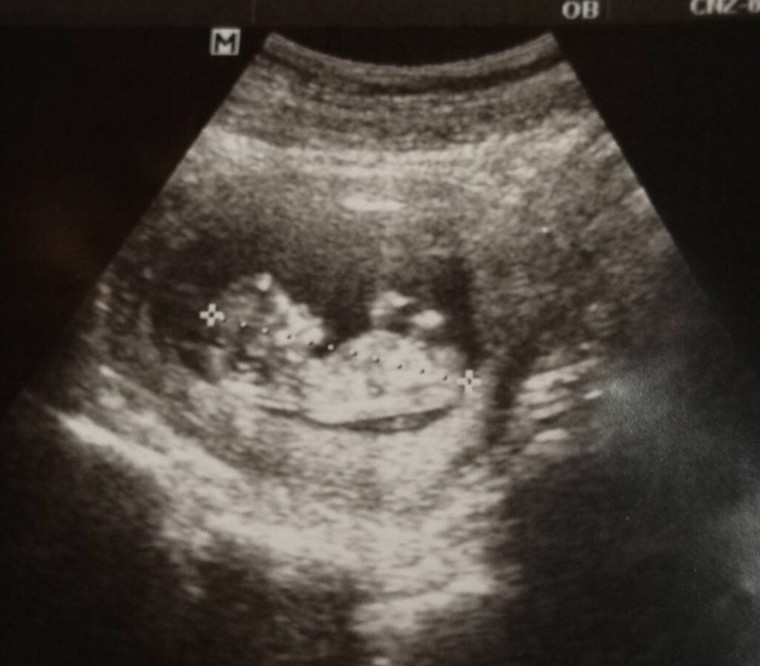

12 week 1 วันค่า เพิ่งซาวด์มาเมื่อวานเลยค่ะดิ้นเก่งมาก🥰